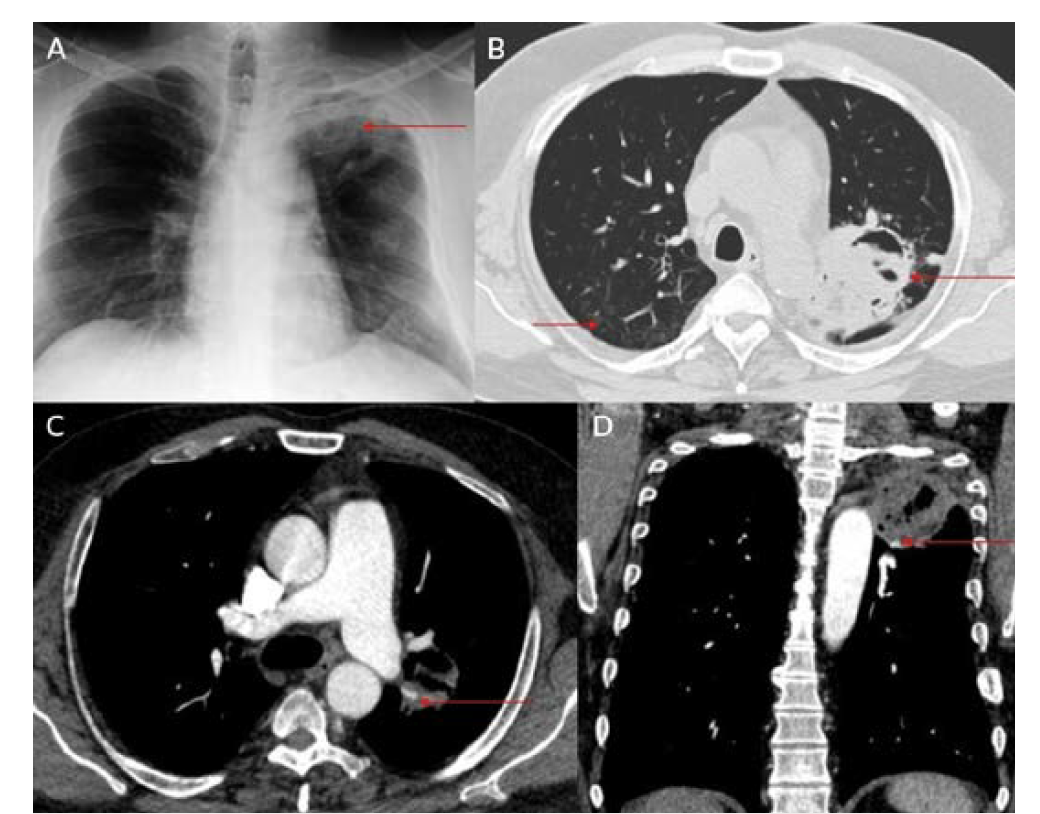

Eight patients were included during this study period; all were men between ages 34 and 61 (Table 1). Positivity to COVID-19 RTPCR test was detected over a period of 2 to 6 months prior to the acute hemorrhage. Six patients presented with massive hemoptysis; 2 presented with severe epistaxis. A contrast-enhanced computed tomography angiography was done in all patients. All 6 patients who presented with massive hemoptysis were detected to have pulmonary arterial pseudoaneurysms with associated cavitary lesions in the lungs (Figure 2). Among the 2 patients who presented with nasal bleed, 1 had a biopsy and culture-proven invasive fungal sinusitis with an internal maxillary artery pseudoaneurysm, probably of mycotic etiology. The second patient also diagnosed with invasive fungal sinusitis had multiple sinonasal debridements outside before presenting with massive epistaxis wherein a diagnosis of internal carotid artery pseudoaneurysm was made, probably secondary to iatrogenic or mycotic etiology. The presence of concomitant COVID-19 infection in these patients predisposed them to impairment of cell-mediated immunity, immune dysregulation, and a decrease in CD4 and CD8 counts, increasing their vulnerability to fungal infections. In 6 patients it was possible to obtain samples for fungal elements through biopsy. Endovascular embolization was performed under local anesthesia in 7 patients, and under general anesthesia in 1 patient. Different embolic agents were used: coils (Figures 3A and 3B), Amplatzer vascular plug (Abbott) (Figures 4A and 4B, Figures 5A and 5B), and glue (Figures 6A and 6B). However, 2 patients underwent lobectomy for extensive parenchymal disease apart from pseudoaneurysm. One patient with pulmonary artery pseudoaneurysm had contrast extravasation into the cavity during the procedure. All patients had cessation of hemorrhage. However, 2 patients required pulmonary lobectomy because of extensive parenchymal disease after embolization for the pseudoaneurysm.

Pulmonary artery pseudoaneurysm is a rare but important entity because of its high risk of life-threatening hemorrhage.2,5,9,10 Peripheral branches of the lower lobe pulmonary artery are most commonly affected.2,5,10 A pseudoaneurysm is different from a true aneurysm because there is no wall except for the hematoma that is surrounding and containing it.6,9,11,12 The etiology of a pulmonary artery pseudoaneurysm is inflammatory erosion secondary to tuberculosis (Rasmussen aneurysm), necrotizing pneumonia, bacterial endocarditis, mucormycosis, or vasculitides (Marfan syndrome, Behçet’s disease, etc.). Other causes include necrotic cavitary lung carcinoma, congenital heart disease, and traumatic injury. Iatrogenic pseudoaneurysm secondary to pulmonary artery catheter placement has also been reported.4-6,9-11 Internal maxillary artery pseudoaneurysm is rare and is more commonly encountered following trauma and iatrogenic injury (Figures 8A and 8B).7,8,13 These patients present with massive or moderate bleeds, which can lead to death in about 50% of cases if left untreated.2,4 The most common artery leading to hemoptysis is the bronchial artery, which constitutes around 80% to 90%.4,5,13 Hemoptysis related to the pulmonary artery constitutes around 10%.10,14 Multidetector computed tomography (MDCT) pulmonary angiography is the modality of choice to diagnose pulmonary artery aneurysms.2,9,10,12 It provides detailed information about the presence, number, size, shape, and origin of pulmonary artery aneurysms.2,9,10 MDCT also allows detailed assessment of the orientation and size of the aneurysmal sac and size of the neck on multiplanar reconstruction.2,10 It also gives an overall idea about the pathology, and the involved lung segment eventually helps in planning the treatment accordingly.4,10,12,14 Digital subtraction angiography has the advantage of allowing endovascular intervention at the time of diagnosis.4,12,14 Ultrasound and magnetic resonance imaging are also used in cases of aneurysms involving neck vasculature.2,14,12

Endovascular intervention is a minimally invasive technique that is used to treat these types of pseudoaneurysms.4-6,11 Pulmonary artery pseudoaneurysms can be treated with multiple techniques, such as coil embolization of the involved artery, plug placement within the involved artery, glue embolization of the aneurysm, and placement of a stent graft across the aneurysm.4,10,11 If the aneurysm is peripherally placed and is not accessible via a transarterial approach, ultrasound-guided injections such as thrombin or glue can be tried.14 The endovascular approach is minimally invasive compared with surgery.9,10 Mortality, morbidity, and complication rates following endovascular intervention are lower compared with surgery.5,11 Hospital stays following endovascular intervention are usually lower.9,10 Endovascular embolization has an initial success rate of 95%, and surgery is reserved for those patients where multiple sittings of embolization have failed.4,5,10